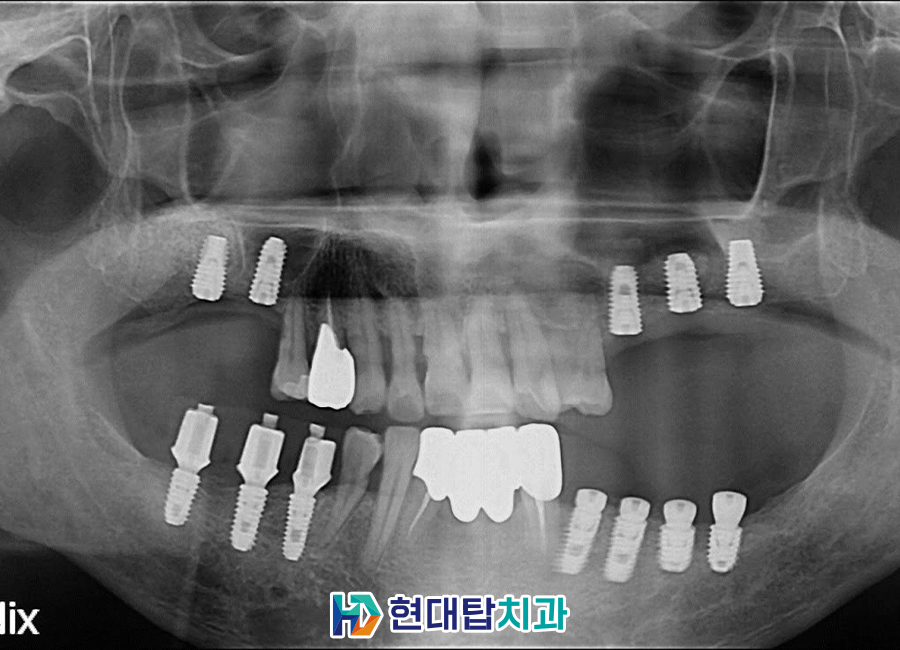

단단하게 뼈가 만들어진 후

위쪽 임플란트를 식립한 모습입니다.

아래쪽은 중간 연결기둥을 체결하였고

충치치료들을 완료하였습니다.

최종 보철까지 완성된 모습입니다.

오른쪽 위 작은 어금니의 경우

처음 내원 당시 본을 떠서 떼우는

인레이로 진행하였습니다.

하지만 충치가 심해져

치아 전체를 덮어 씌우셨고

씌운 후에도 식사하실 때의

통증으로 인해 발치 후

임플란트 진행 중입니다.